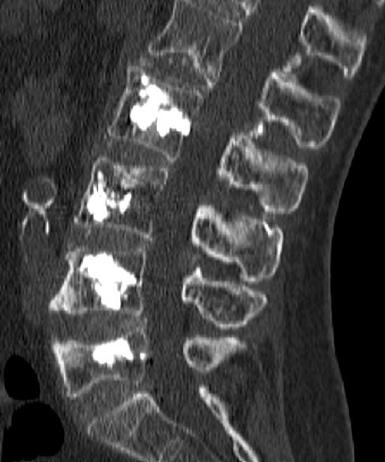

Vertebroplasty is a minimally invasive, image-guided procedure used to stabilize weakened vertebrae and provide rapid pain relief. It consists of injecting medical-grade bone cement (PMMA) into the vertebral body, restoring mechanical strength and reducing micromovements responsible for pain.

In oncologic patients, vertebroplasty is not only a stabilization technique. It is frequently combined with tumor ablation (radiofrequency, microwave, cryoablation) to:-

Achieve local tumor debulking

Stabilize the vertebra after tumor destruction

The procedure is performed under conscious sedation (local anesthesia with intravenous analgesia and mild sedation) or, in selected cases, general anesthesia.-

Percutaneous access through the pedicle under CT or fluoroscopic guidance

Precise needle positioning within the vertebral body

- Controlled injection of bone cement with real-time monitoring